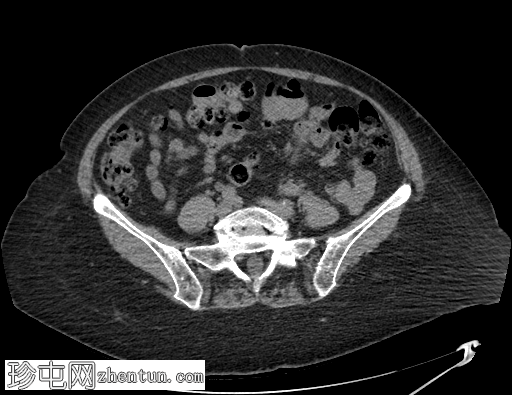

轴位

平扫

弥漫性结肠憩室病,无憩室炎证据。

横结肠中段可见一憩室,动脉期开始出现异常造影剂外渗,门静脉期增多,憩室腔内亦可见造影剂外渗,提示憩室出血伴活动性动脉出血。